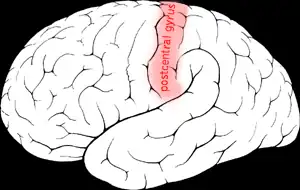

Giro pós-central no cérebro humano. | |

O giro pós-central é uma proeminente estrutura do lobo parietal do cérebro humano e o principal local do córtex somatossensorial primário (S1). Essa área é responsável por processar informações sensoriais táteis e proprioceptivas. No giro pós-central, existe um "mapa" sensorial chamado de homúnculo sensorial, que representa a superfície do corpo de forma distorcida, refletindo a densidade de receptores sensoriais em cada região[1]. O córtex somatossensorial foi detalhado inicialmente pelos estudos de Wilder Penfield e posteriormente refinado por pesquisas modernas, que destacaram a predominância da área de Brodmann 3 como o verdadeiro receptor das projeções talâmicas[2].

Anatomia

O giro pós-central está localizado no lobo parietal, logo atrás do sulco central, sendo delimitado por:

- Fissura longitudinal medial (medialmente);

- Sulco central (rostralmente);

- Sulco pós-central (caudalmente); e

- Sulco lateral (inferiormente).